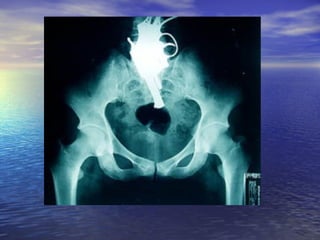

ALTERACIONES ORTOPEDICAS Función del pie   Sustentación y locomoción 80% de la población presenta algún tipo  de alteración de apoyo Alteración de biomecánica del pie Aumento de presiones de apoyo :   obesidad- talla mayor-  Limitación  movilidad  articular del pie-  Deformaciones óseas  -  Alteraciones de columna vertebral  - desigualdad de  miembros inferiores  Valoración :  individuo descalzo, sin medias marcha deformaciones cantidad, calidad y desplazamiento almohadilla plantar Rx ambos pies:  frente-perfil con apoyo monopódico-3/4 oblicua A-B-C-S

ALTERACIONES ORTOPEDICAS Funcióndel pie Sustentación y locomoción 80% de la población presenta algún tipo de alteración de apoyo Alteración de biomecánica del pie Aumento de presiones de apoyo : obesidad- talla mayor- Limitación movilidad articular del pie- Deformaciones óseas - Alteraciones de columna vertebral - desigualdad de miembros inferiores Valoración : individuo descalzo, sin medias marcha deformaciones cantidad, calidad y desplazamiento almohadilla plantar Rx ambos pies: frente-perfil con apoyo monopódico-3/4 oblicua A-B-C-S